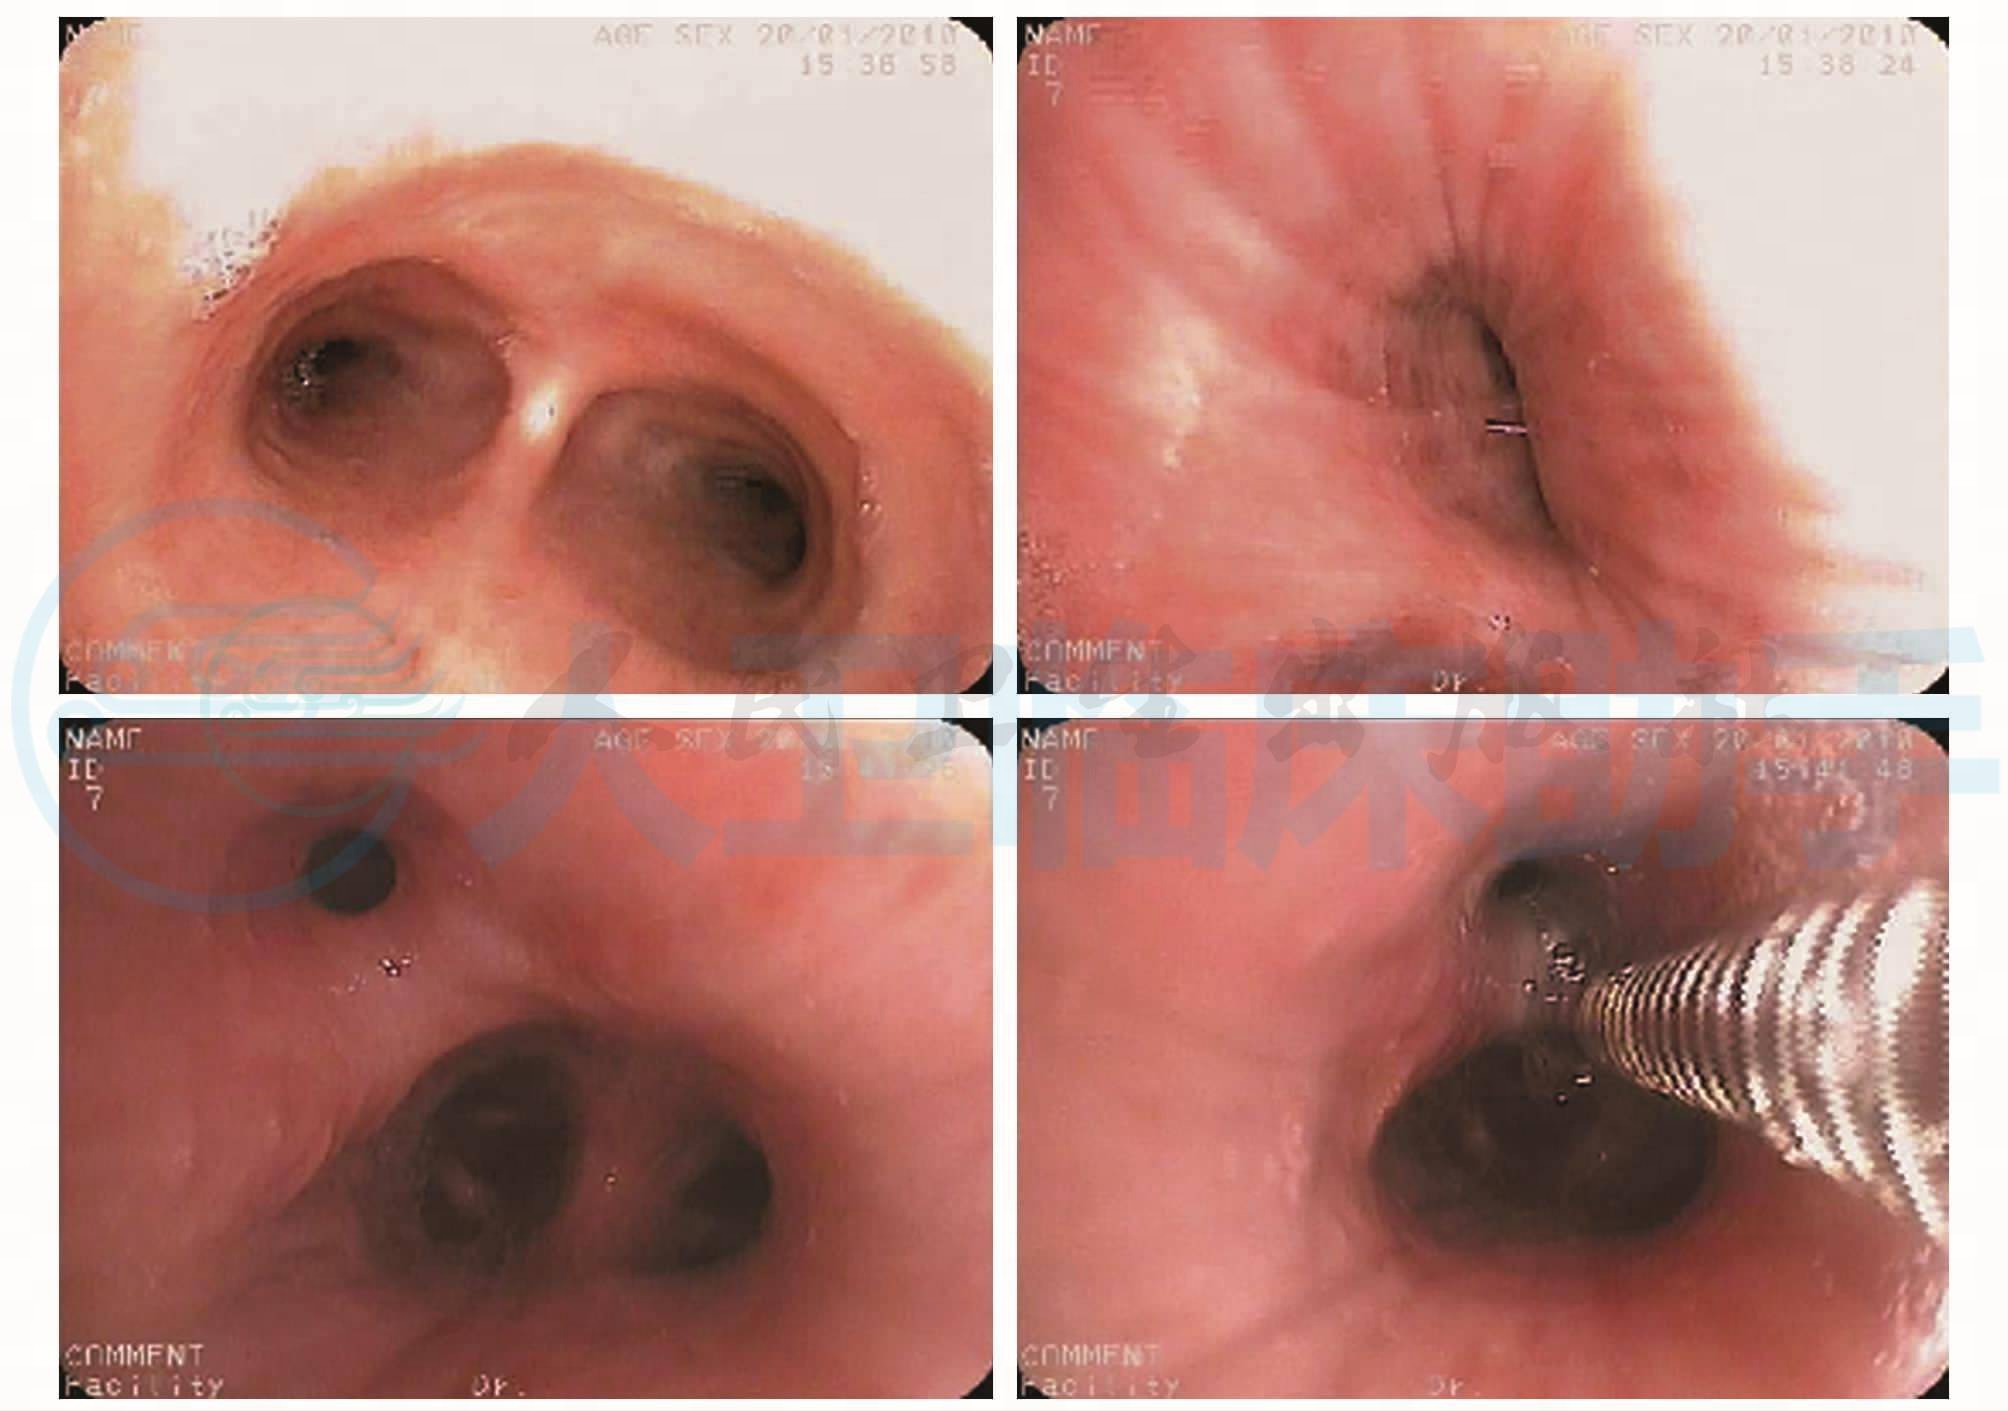

转入呼吸科后予患者完善如下检查:①肺功能检查,结果提示混合性肺通气功能障碍,FEV1/FVC 42%,FVC 0.8L,FVC/预计值39%,小气管功能重度减退。②完善气管镜检查,结果回报:气管支气管广泛狭窄,以左肺下叶基底段支气管和右肺中叶支气管为著(图2)。

图2 纤维支气管镜见气管支气管广泛狭窄,以左肺下叶基底段支气管和右肺中叶支气管为著